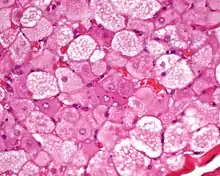

Hibernoma (aumento intermedio).